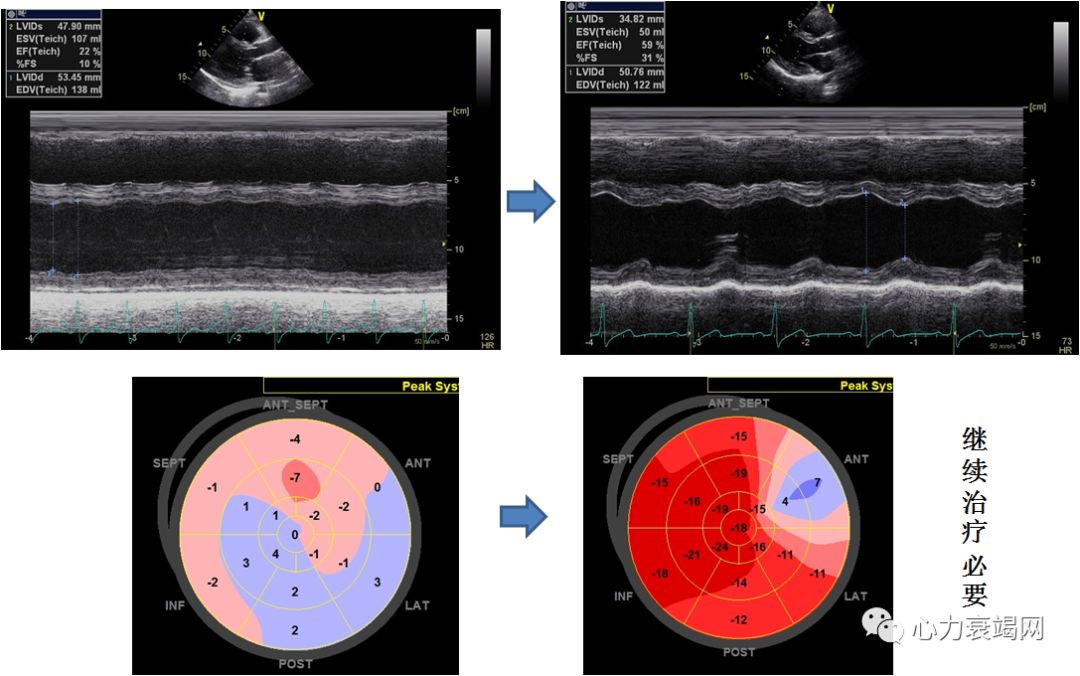

外院ECHO:扩张型心肌病,左房、左室扩大,左室舒张、收缩功能降低,二尖瓣少量返流,EF27- 45%。

治疗前

2个月后

激素及抗心衰治疗后

伴心衰的血管炎患者,在治疗心衰的同时,应积极治疗原发病(激素,免疫抑制剂)。早诊断早治疗改善预后。部分患者LVEF可逆转,但需继续心衰药物治疗。